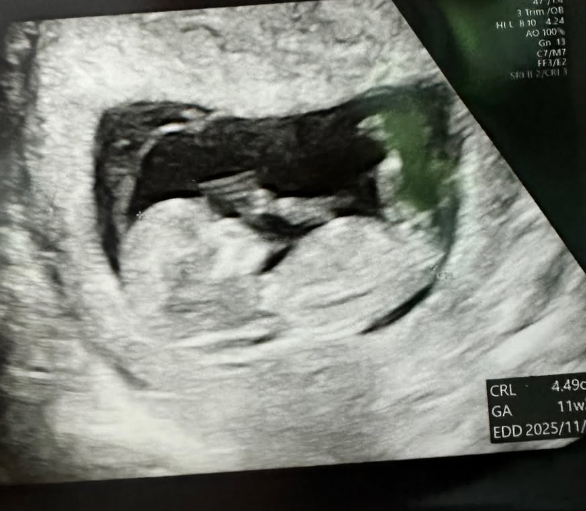

트루디가 올린 금똥이 태아 초음파 사진 사진트루디 SNS

트루디가 올린 금똥이 태아 초음파 사진 [사진=트루디 SNS]

트루디는 9일 자신의 사회관계망서비스(SNS)에 "안녕하세요. 트루디입니다. 행복한 '가정의 달' 잘 보내고 계신가요? 지금도 믿기지 않지만, 제가 올해 11월에 엄마가 됩니다"라는 글과 함께 태아 초음파 사진을 게재했다.

이어 "태명은 금똥이에요. 배가 너무 나와서 X인 줄 알았는데, 알고보니 금덩이라서요. 축하해 주신 모든 분들 감사합니다. 아직 많이 서툴지만, 많이 도와주세요. 사랑해요"라고 덧붙였다.